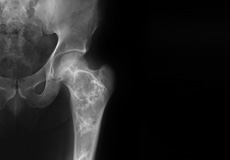

Septic Arthritis

Septic arthritis also called as infectious arthritis, is characterized by joint inflammation due to a bacterial or fungal infection that usually affects the large joints of the body such as knee or hip.